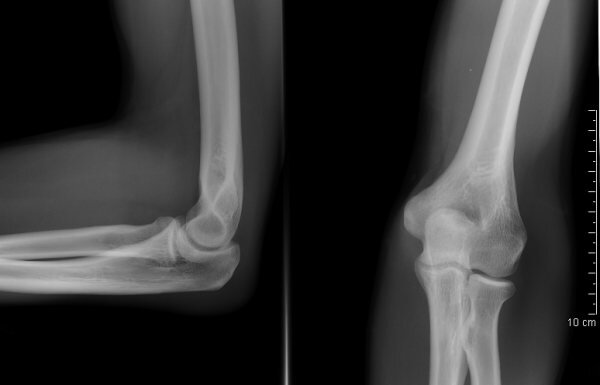

КТ локтевых суставов (или мультиспиральная компьютерная томография локтя) - это томографический, то есть послойный, и рентгенологический, то есть с использованием рентген-лучей, метод сканирования. В ходе него высокотехнологичный томограф осуществляет многочисленные снимки структур локтевого соединения под разными углами, а компьютер на основании полученных сканов выстраивает объемные реконструкции сочленения локтевой, лучевой и плечевой костей. Результатом сканирования являются томограммы, на которых врач может увидеть патологические костные изменения размером до 1 мм. Качество и цена КТ локтевых суставов во многом зависят от срезовой мощности томографа и применения контрастного усиления. В диагностических центрах Санкт-Петербурга установлены томографы мощностью от 4 до 128 срезов за один оборот рентгенологической трубки. Чем больше оборотов может делать КТ аппарат, тем детальнее и информативнее будут снимки.

Оценка состояния суставов, костей и мягких тканей локтевой области происходит путем сканирования руки рентгеновскими лучами с дальнейшей обработкой данных на компьютере. Итогом процедуры является полная реконструкция зоны локтя в виде трехмерной модели. Полученные в ходе обследования снимки (томограммы) хорошо отображают патологические изменения в структуре костей и мягких тканей.

Подготовка результатов расшифровки и описания снимков занимает от 40 минут до 2 часов. В ходе процедуры интерпретации рентгенолог диагностического центра детально изучает томограммы на предмет наличия патологий, переломов и трещин костей, нарушения целостности локтевых суставов и соответствие суставных структуры нормативам. Результаты выдаются пациенту на пленочных и цифровых носителях и в виде письменного рентгенологического заключения, с которыми пациента направляют на консультацию к лечащему врачу. На основании заключения и предыдущих обследований он устанавливает диагноз и назначает адекватное лечение.